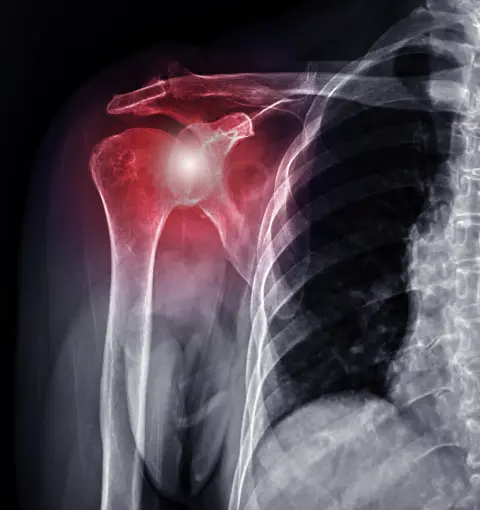

Luxação do Ombro

A luxação ocorre quando o osso do braço sai da articulação do ombro. Realizamos tratamento conservador e cirúrgico para estabilização articular.

O ortopedista especialista em ombro em Goiânia trata diversas condições como tendinite, bursite, lesões do manguito rotador, luxação do ombro, rompimento de tendões, artrose, capsulite adesiva (ombro congelado), fraturas e outras patologias que afetam a articulação do ombro.